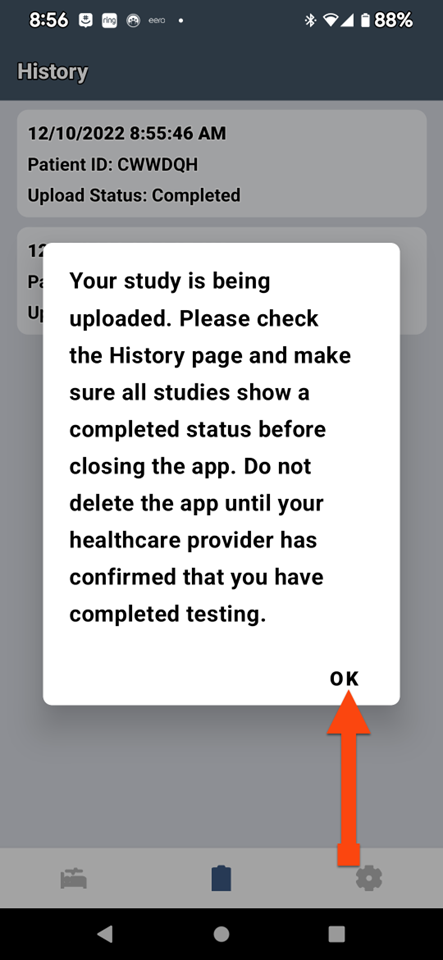

SLEEPIMAGE APP (Android)

SLEEPIMAGE APP (Android)

SLEEPIMAGE APP (Android)

SLEEPIMAGE APP (Android)

SLEEPIMAGE APP (Android)

SLEEPIMAGE APP (Android)

SLEEPIMAGE APP (Android)

SLEEPIMAGE APP (Android)

SLEEPIMAGE APP (Android)

SLEEPIMAGE APP (Android)

SLEEPIMAGE APP (Android)

SLEEPIMAGE APP (Android)

SLEEPIMAGE APP (Android)

SLEEPIMAGE APP (Android)

SLEEPIMAGE APP (Android)

SLEEPIMAGE APP (Android)

SLEEPIMAGE APP (Android)

SLEEPIMAGE APP (Android)

SLEEPIMAGE APP (Android)

SLEEPIMAGE APP (Android)

SLEEPIMAGE APP (Android)

SLEEPIMAGE APP (Android)

SLEEPIMAGE APP (Android)

SLEEPIMAGE APP (Android)

SLEEPIMAGE APP (Android)

SLEEPIMAGE APP (Android)

SLEEPIMAGE APP (Android)

SLEEPIMAGE APP (Android)

SLEEPIMAGE APP (Android)